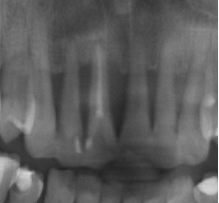

Bogata w płytki i leukocyty fibryna jest stosowana w regeneracji tkanek od ponad 15 lat. Pozytywny wpływ PRF (platelet-rich fibrin) na regenerację tkanek miękkich jest niewątpliwy, bezsporny i częściowo udowodniony w badaniach klinicznych i analizach biochemicznych. Wpływ PRF na regenerację tkanki kostnej jest obserwowany klinicznie, ale nadal niedostatecznie poznany jest mechanizm tego zjawiska.

Platelet- and leukocyte-rich-fibrin has been used in regeneration of tissue for more than 15 years. The positive influence of PRF on the regeneration of soft tissue is undoubtedly, without question and partially proven in clinical studies and biochemical analysis. Influence of PRF on regeneration of bone tissue is observed clinically but the mechanism of this phenomenon is still not sufficiently known.